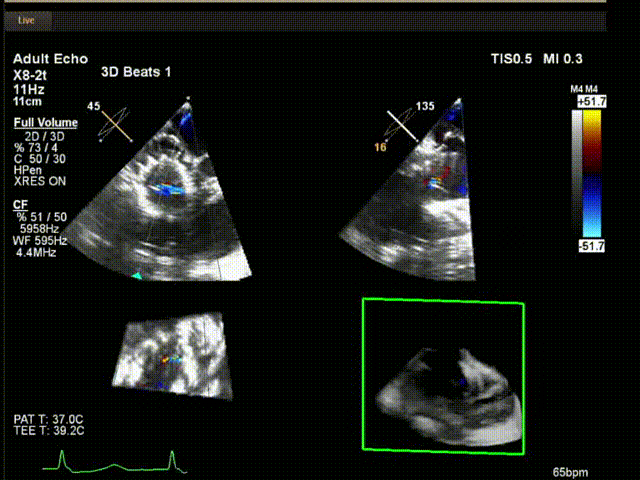

術(shù)中超聲

陸方林教授通過(guò)遠(yuǎn)程線上帶教的方式,與林逸賢教授團(tuán)隊(duì)共同完成了此次LuX-Valve Plus人工瓣膜的首例植入。術(shù)后食道超聲提示三尖瓣反流完全消失,無(wú)瓣周漏,且LuX-Valve Plus人工瓣膜的兩個(gè)夾持鍵成功抓取瓣葉,錨定牢固,人工瓣膜穩(wěn)定性良好。